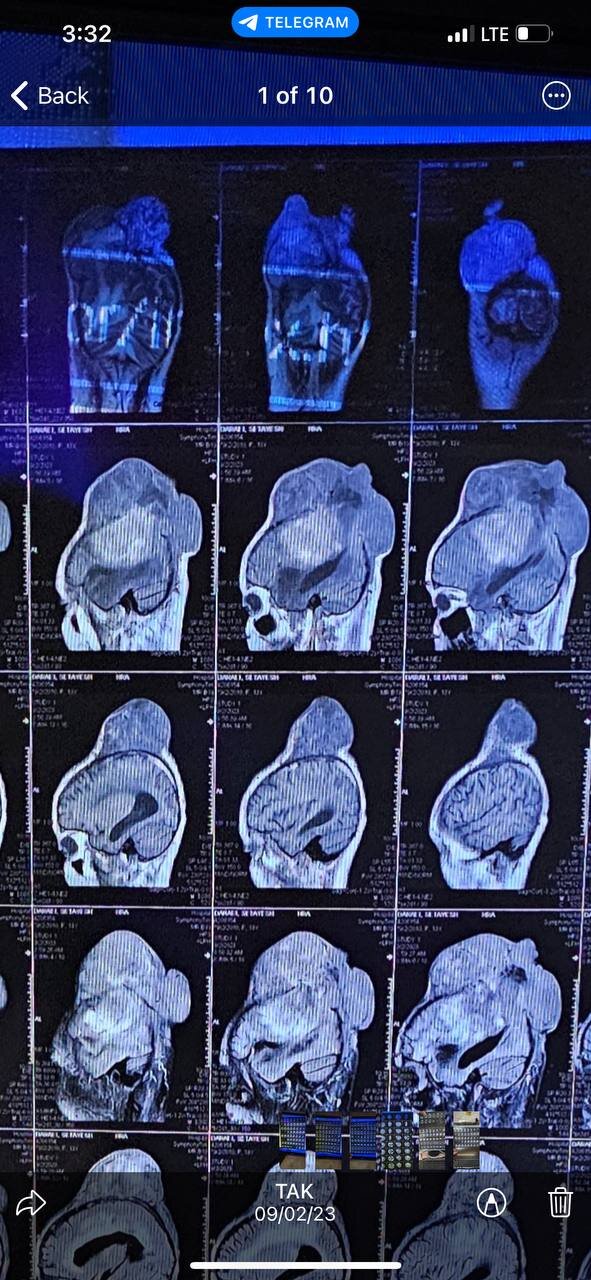

این دختر ۱۳ ساله یک نوبت در تهران تحت عمل جراحی قرار گرفته بود، اما به دلیل این که نتوانسته بودند تومور را به دلیل ریسک بالا، کامل تخلیه کنند، دو ماه پس از عمل جراحی در آن مرکز، با عود شدید مواجه میشود. در این مدت استخوان و پوست سر به شکل وحشتناکی درگیر و به شکل کلاهخود شده بود. خانواده این کودک برای درمان فرزندشان سختی زیادی کشیدند و حتی از پزشکان دو کشور ترکیه و آلمان هم تقاضای کمک کرده اما پذیرش نشده بودند. در نهایت سراغ ما آمدند و همان ابتدا نسبت به عوارض و ریسک بسیار بالای این جراحی توضیحات کامل را به آنها دادیم. اما در نهایت این دختر و خانوادهاش شرایط را پذیرفتند و ما هم تصمیم به انجام جراحی گرفتیم. این عمل در زمانی نزدیک به هفت ساعت همراه با دکتر محمد ماندگاری، فوقتخصص گوش، حلق و بینی و دکتر حسن عبداللهی، متخصص بیهوشی در بیمارستان شهید رهنمون یزد انجام شد و کادر پزشکی دانشگاه علوم پزشکی شهید صدوقی یزد و بیمارستان شهید رهنمون هم شرایطی را به گونهای برای ما فراهم کردند که موفقیت این جراحی افزایش پیدا کند.

اول این که چنین موارد کم است اما به طور کلی عملهای جراحی مغز بسیار حساس هستند و ریسک مرگ و میر بالایی دارند. توده موجود در سر این کودک حدود ۳.۵ کیلوگرم وزن داشت اما متفاوت از توده ۳.۵ کیلویی در داخل عضوی مثل شکم یا قفسه سینه است. مغز حدود یک کیلو و ۷۰۰ یا ۸۰۰ گرم وزن دارد. این تومور در سر این دختر بچه رشد کرده و نیمی از نیمکره سمت چپ مغز را گرفته بود، باقی آن پوست سر را به سمت بالا هل داده و رشد کرده بود. انجام چنین جراحیهایی ریسک مرگ دارد و تقریبا تیمهای پزشکی قبول نمیکنند که چنین ریسکی را بپذیرند. از سوی دیگر نبود تجهیزات بسیار حرفهای و هایتک هم انجام این عمل را سختتر میکند. اما در نهایت انجام شد و این کودک اکنون در وضعیت عمومی خوبی قرار دارد و به زودی ترخیص میشود تا برای تکمیل مراحل درمانی، رادیوتراپی و شیمیدرمانی را آغاز کند.

آمار شیوع تومور در دنیا چیزی حدود ۰٫۲ تا ۰٫۵ درصد است. انواع و گریدهای مختلفی هم دارند، خوشخیم و بدخیم. برخی تومورها مربوط به سرطان مغز هستند و برخی دیگر هم از سایر نقاط بدن به مغز سرایت میکند. دختربچهای که در بیمارستان یزد تحت عمل جراحی قرار گرفت، گرید سه، یک تومور خوشخیم اما بسیار تهاجمی و عودکننده بود اما به طور کلی افراد و خانوادههای زیادی در کشور خودمان از تومورهای مغزی رنج میبرند، به همین دلیل قطعا به یک مرکز نیاز داریم که تنها درباره تومورهای مغزی به بیماران خدمات ارائه کند.